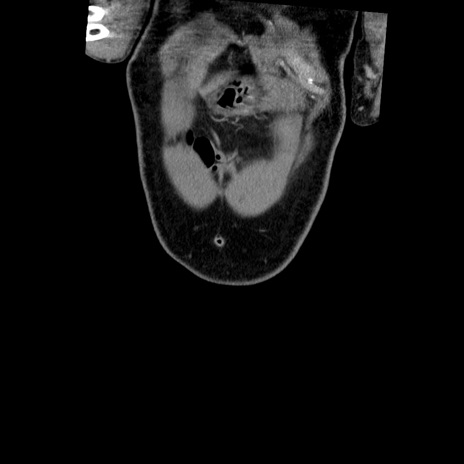

横断像

【症例】50歳代男性

【主訴】腹痛

【現病歴】AVMからの被殻出血のため回復期リハ病棟入院中。 本日午後3時頃急に下腹部痛が出現した。

【既往歴】AVM、被殻出血、虫垂炎、高血圧

【身体所見】意識晴明、左半身不全麻痺、会話の理解は良好、36.5°C、腹部:膨隆、全体に板状硬、下腹部正中に圧痛点あり、反跳痛-、筋性防御不明、右下腹部にope scar

【データ】WBC 9400、CRP 0.06